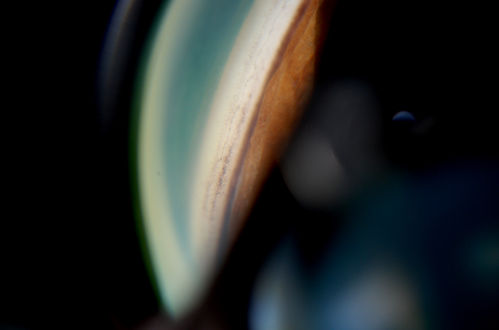

Gonioscopy; Scattered Peripheral Anterior Synechiae

Patient comes in for evaluation for glaucoma. Patient also has a history of Uveitis. Last flare up was back in 1990. Patient's VA was 20/30, Right eye and 20/40-1, Left eye. Slit Lamp Gonioscopy reveals iris bow with scattered PAS around the angles of the anterior chamber. You can also see pigmentation in the trabecular meshwork. Patient will follow up in 3-months.